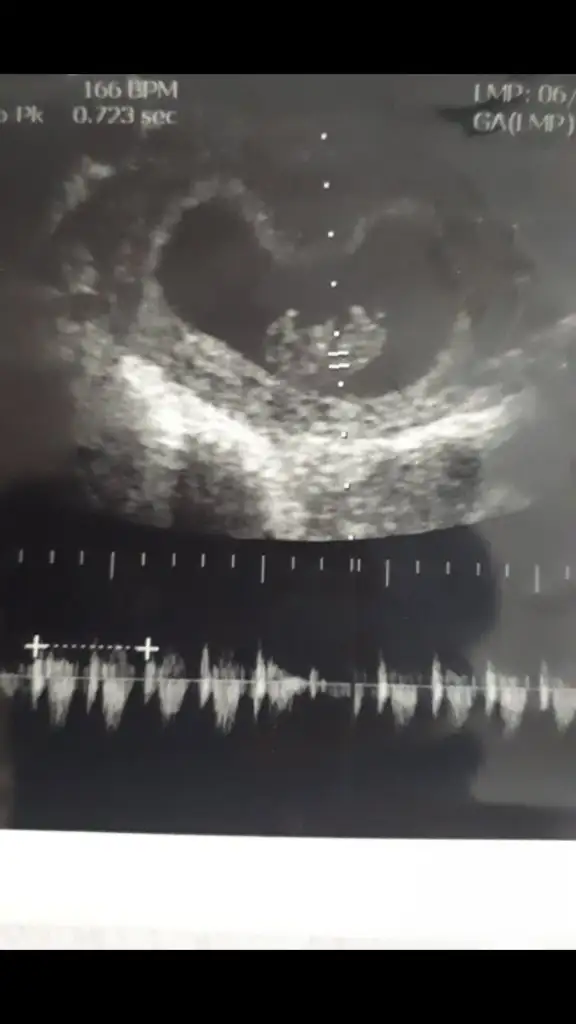

Şekil almamışa kız derler seninkide kız olabilir 11 yada 12 hafta paylaşırsınız tekrarKızlar tekrar paylaşıyorumilki 6 haftalık 2. 9 haftalık rica etsem bakabilir misiniz

11+6 haftalik